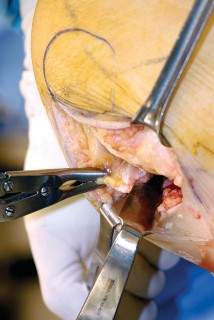

القوالب المسبقة (Preoperative Templating):

يتم استخدام الأشعة السينية لتحديد حجم وموضع المكونات المزروعة بدقة قبل الجراحة.

- تحرير الأنسجة الرخوة: يتم قطع الغضروف الهلالي لتحرير الأنسجة الرخوة من عظم الظنبوب، ويتم تطوير سديلة تحت السمحاق في نمط دائري حول الظنبوب. يُمدد هذا التحرير خلفيًا لضمان توازن الأربطة.

-

تصحيح التشوه:

الهدف هو تحقيق تصحيح طفيف للتشوه، مع وجود رخاوة كاذبة طفيفة عند تطبيق ضغط تفحجي في نهاية الإجراء. يجب تجنب التصحيح المفرط.